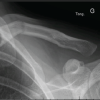

The surgical technique involved general anesthesia, aseptic precautions, and antibiotic coverage. A supra-clavicular incision was used to access the fracture site, preserving superficial nerves. Pointed reduction forceps were used to handle fracture fragments (Fig. 1a) and extra periosteal suture material was used for fragment reduction (Fig. 1b). In comminuted fractures, 2.7 mm cortical interfragmentary screws were used (Fig. 1c), with the NISE knot technique applied for severe comminution (Fig. 1d). The simplified method of the NISE knot is shown in Fig. 2, referenced from Hu et al. paper [9]. An anatomical clavicular plate was fixed with both non-locking and locking screws (Fig. 1e). Post-surgery, X-rays were taken (Fig. 3). Arm-to-body strapping was implemented for the early post-operative phase. Patients were discharged on the third post-operative day after one dressing change and given a body banian for protection. Suture removal was scheduled for the 11th day post-operation.